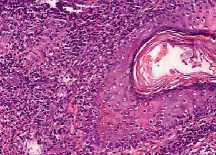

Leishmaniasis background and histology presentation. The World Health Organization (WHO) has selected cutaneous leishmaniasis as a neglected tropical disease (NTD) with growing, uncontrolled, and ignored infection affecting millions of people every year [14, 9]. It is unfortunately one of the world’s most neglected poverty-related diseases, affecting the poorest people in developing countries and it is associated with risk factors like malnutrition, immune system deficiency, migration, inadequate education, illiteracy, gender inequality, and a shortage of services [1]. Furthermore, only eight countries in the world contribute to 90% of leishmaniasis cases: Afghanistan, Algeria, Brazil, Iran, Pakistan, Peru, Saudi Arabia, and Syria [12]. It is a vector-borne infection caused by the protozoan parasite Leishmania. The vector is the female sand-fly. The lesions of cutaneous leishmaniasis vary in presentation ranging from a single self-limited skin lesion to multiple large destructive and ulcerated lesions on mostly the exposed parts of the body such as face, forearms, and lower legs [2]. Skin biopsy is considered the gold standard method for confirmation of diagnosis. The presence of large epitheloid granulomas and small hematoxylinophilic LD bodies (that are round, uniform in appearance, intracytoplasmic and sometimes distributed around the outer rim of the vacuoles) is critical for diagnosis and confirmation of leishmaniasis [4]. Large granulomas are visible at 10X but the smaller hematoxylinophilic bodies (around 3-4mm in size) are usually visible at 40X and can easily be missed if they are few in number, leading to misdiagnosis. Specialized dermatopathologists are the only ones who can diagnose these accurately based on patient history, clinical features, and laboratory diagnosis. It is thus critical to share the digitized slides of these cases from rural poor remote areas with dermatopathologists (mostly residing in urban centers) for quick diagnosis and accurate management of the patient.

We demonstrate our WSI creation workflow on Leishmaniasis cases, as shown in Figures 1 and 4. An expert pathologist reviewed the cases and annotated granulomas as well as LD bodies on the stitched images and our generated images in Figure 4. To show generalizability of our approach, we also show results on core biopsies of breast, duodenum, stomach, liver, and lymph nodes (Figure 5).